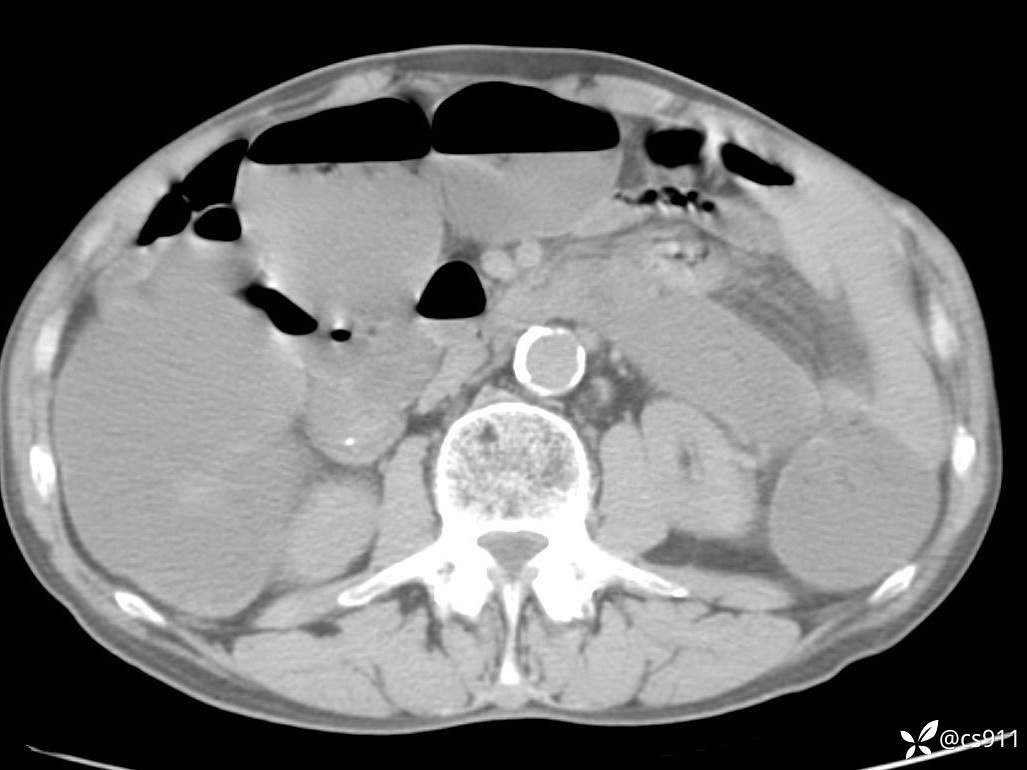

急腹症之急诊CT,原因?答案公布

男,77岁,腹痛、腹胀伴恶心呕吐1天。呕吐胃内容物,非喷射性呕吐,有咖啡色样胃内容物,诉有胃穿孔病史。查体:全腹平,下腹部压痛,全腹无反跳痛,叩诊呈浊音,移动性浊音阴性,肠鸣音减弱,1-2次/分。肛检:直肠未扪及明显肿物,可触及大量粪块。

血淀粉酶(AMY) HH 1859 U/L 35-135